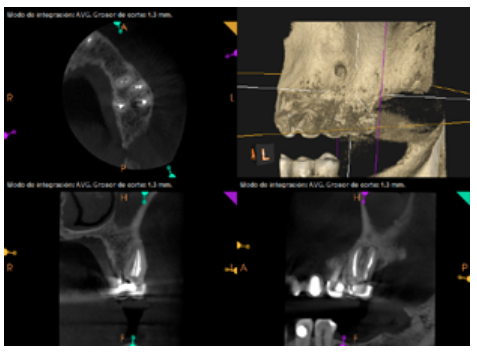

To confirm the endodontic origin and the size of the lesions, tomographic examinations were performed with a slice thickness of 75 microns using CBCT CS8100 (Carestream Dental™), in which radiolucent periapical lesions were observed at the level of 12, 11, 21 (with bicortical involvement), 25 and vestibular roots at 26 (Figures 4 to 8).

Six months later, the patient went for a check-up without any symptoms, both anteriorly and posteriorly. Periapical radiographs showed a decrease in the size of the pre-existing radiolucent periapical lesions (Figures 10 and 11). Given that the lesion on 25 remained to be treated, a control CBCT was performed where improvement at the level of 26 was verified (Figure 12), so microsurgery on 25 was scheduled.

After the microsurgery was performed on 25, the patient had no symptoms and the control tomographies at 12 months (in 25) and at 18 months in the remaining teeth showed regeneration of pre-existing radiolucent periapical lesions on all treated teeth (Figures 13 to 16).